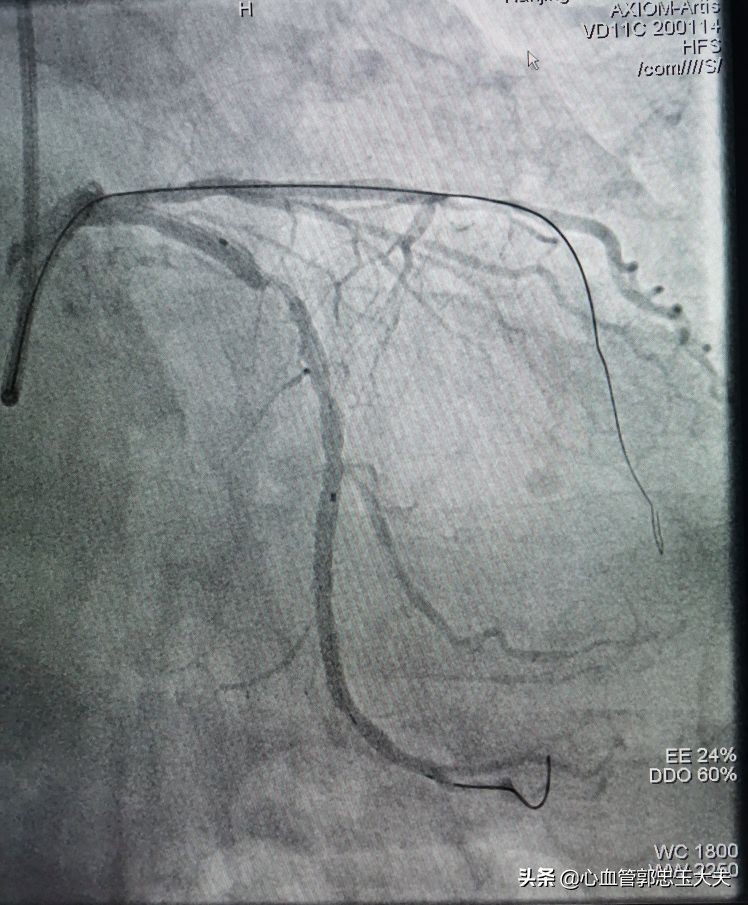

张大爷86岁了,有高血压病史,无烟酒嗜好。因为“反复胸闷头晕数月”入院。冠状动脉CTA示:三支病变,严重钙化合并高度狭窄。行冠脉造影示:前降支中远段钙化,完全闭塞,远端可见血管影。未见明显侧枝循环。(如下图)